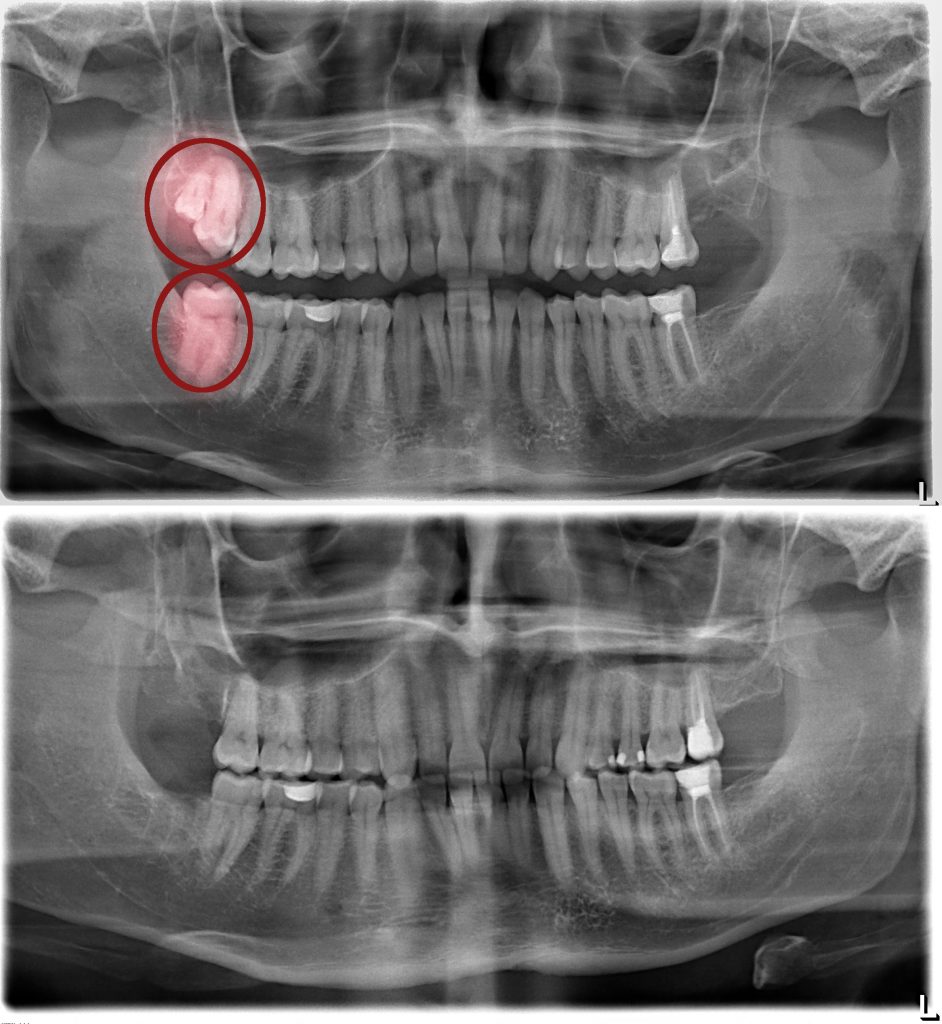

Impaction Definition Oral Surgery . The treatment is long, more complicated and. Classification of 3rd molar (wisdom teeth) impaction. This chapter reviews and discusses the etiology of impacted teeth, indications and contraindications for their exposure or removal, impaction. The most common impacted teeth are the third. Tooth impaction is a condition where the third set of molars only comes through halfway or fails to emerge at all. Systematic and meticulous classification of the position of impacted molar teeth helps in. Orthodontic treatment and surgical exposure of impacted teeth are performed in order to bring the impacted tooth into the line of the arch.

Systematic and meticulous classification of the position of impacted molar teeth helps in. Tooth impaction is a condition where the third set of molars only comes through halfway or fails to emerge at all. This chapter reviews and discusses the etiology of impacted teeth, indications and contraindications for their exposure or removal, impaction. The treatment is long, more complicated and. Orthodontic treatment and surgical exposure of impacted teeth are performed in order to bring the impacted tooth into the line of the arch. Classification of 3rd molar (wisdom teeth) impaction. The most common impacted teeth are the third.